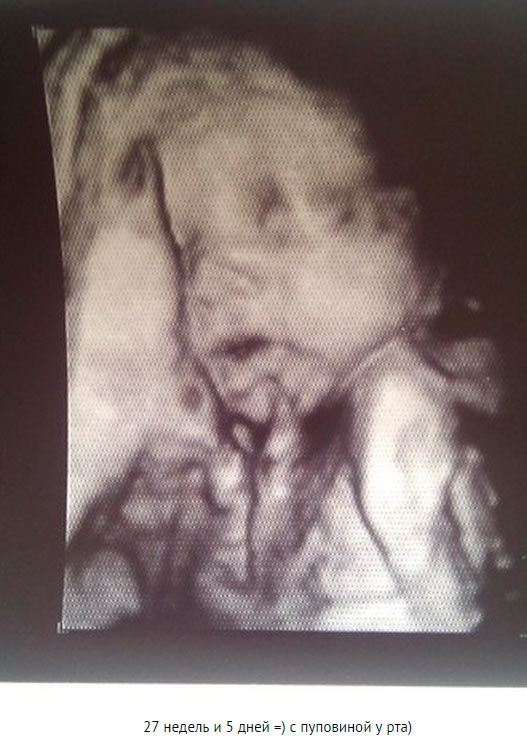

Voici à quoi ressemble le fœtus à la vingt-septième semaine:

Photo échographie: